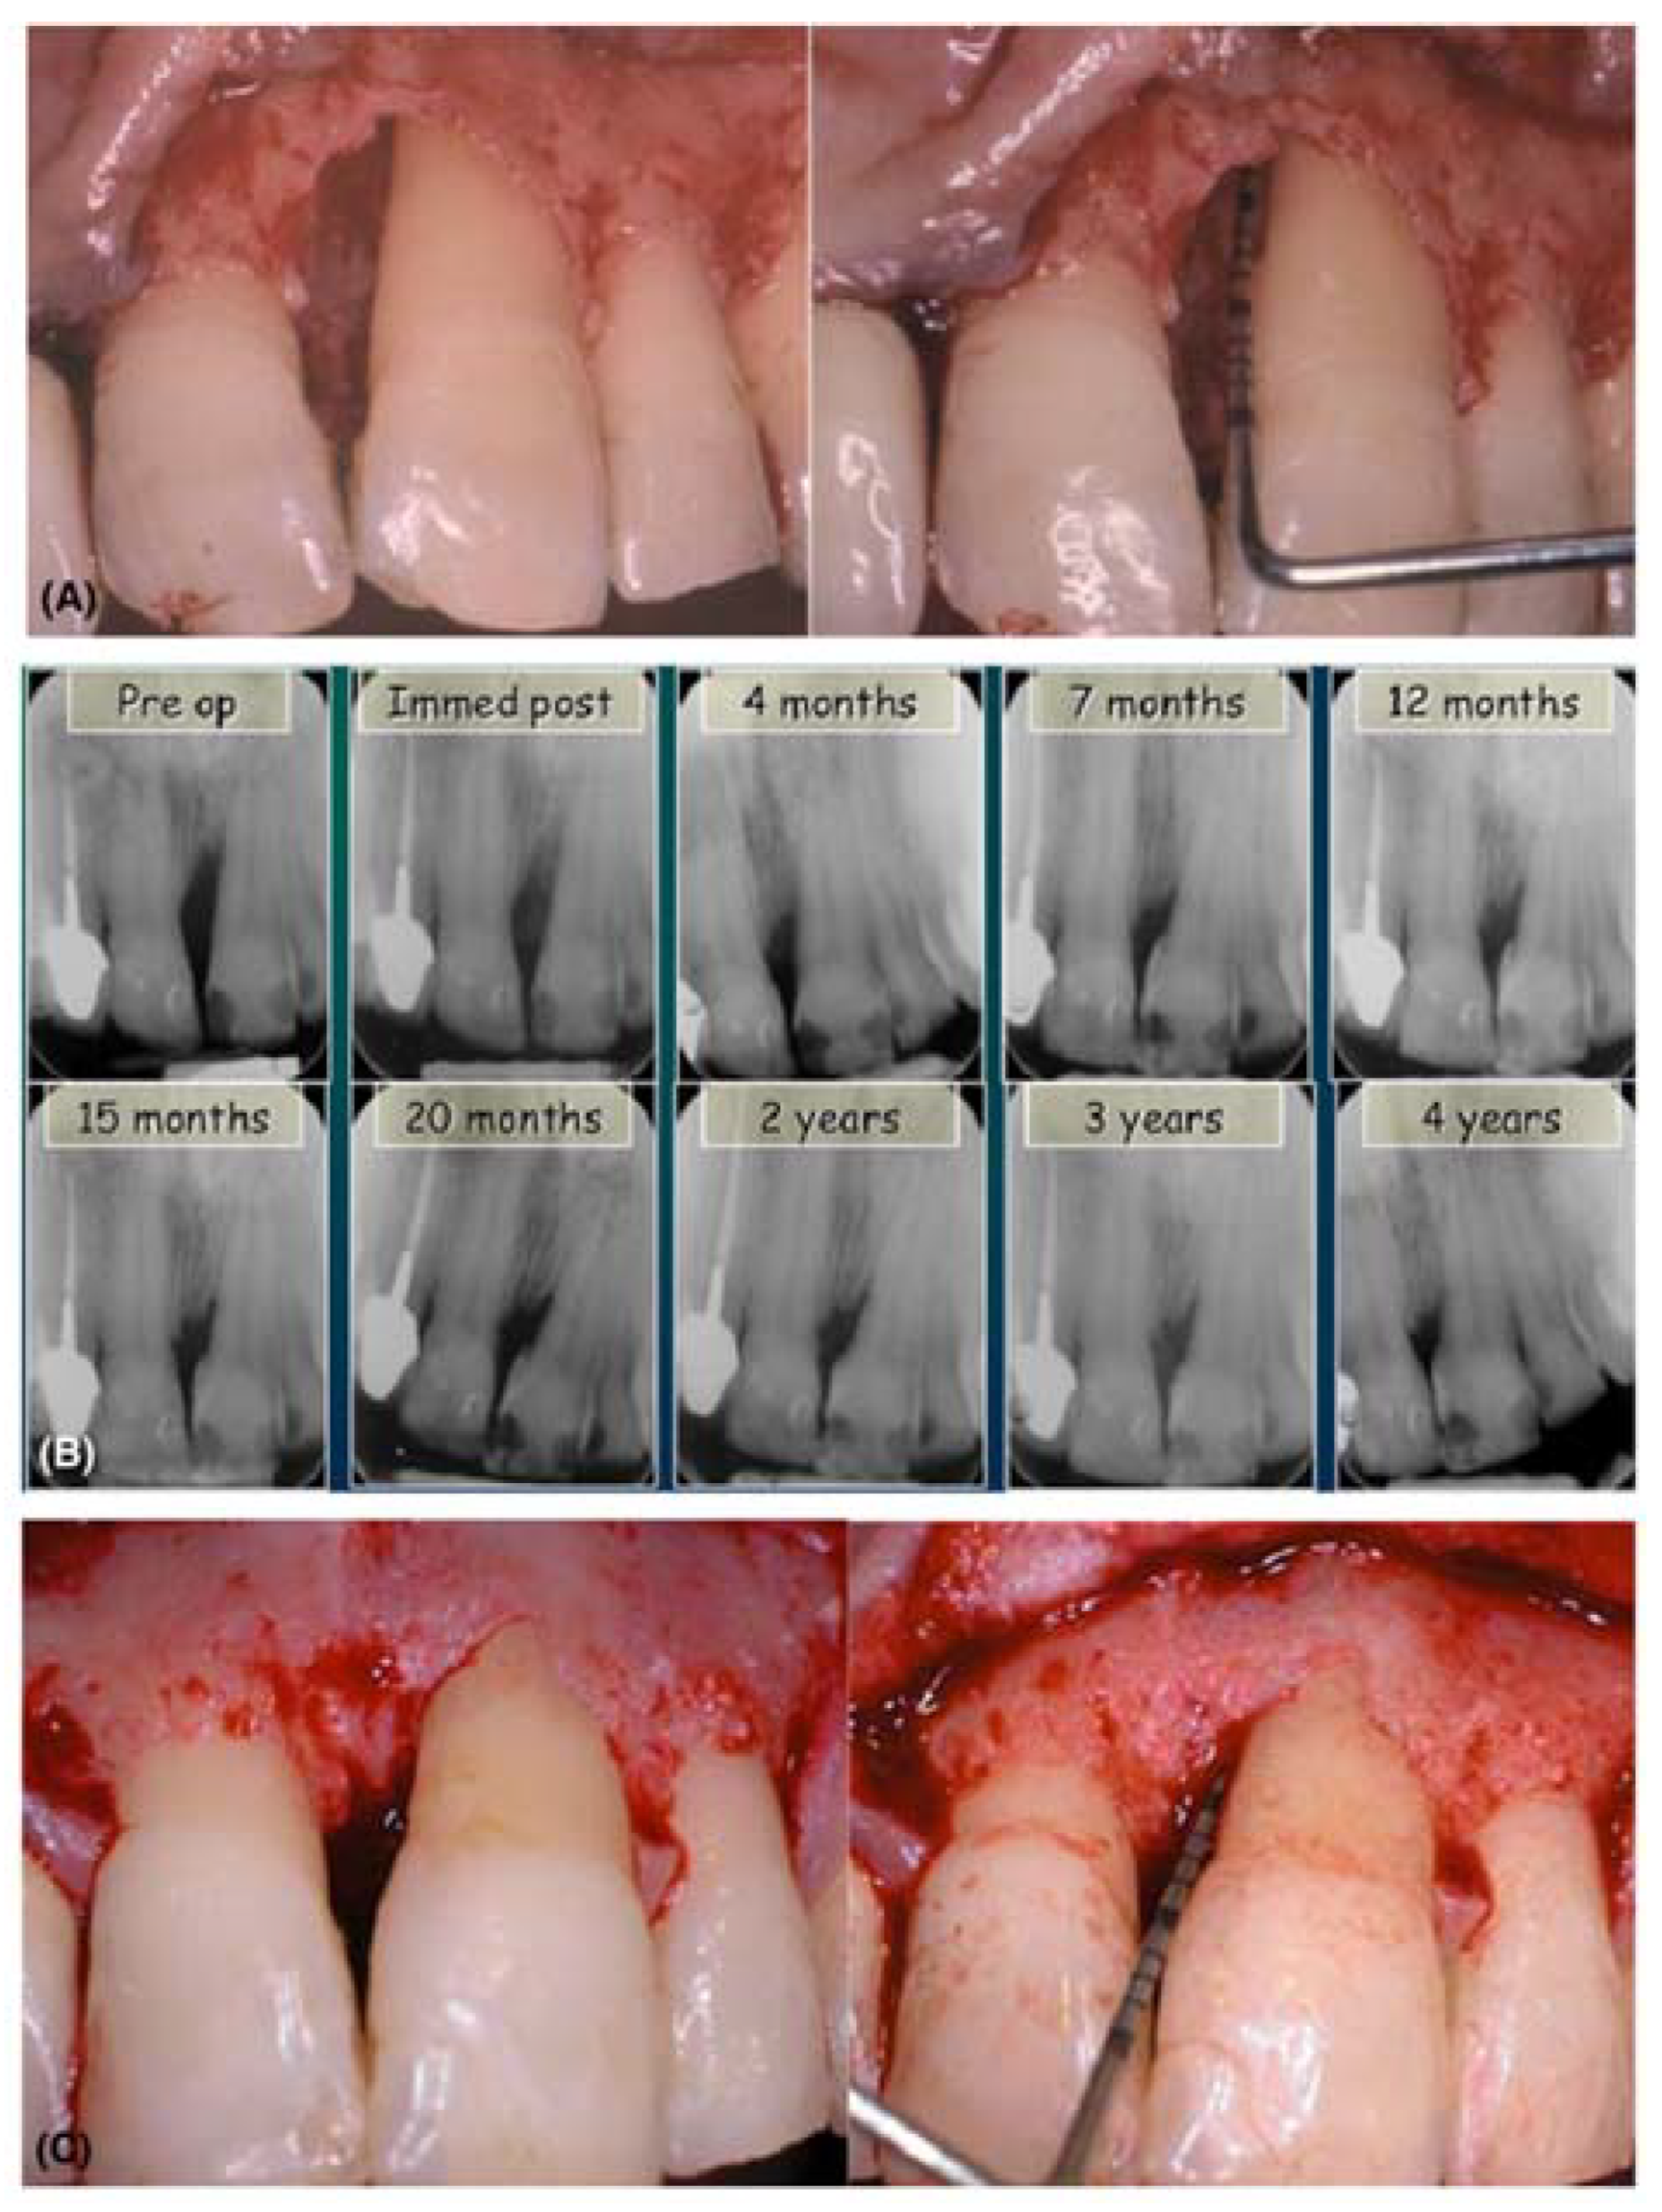

- Hägewald, S.; Spahr, A.; Rompola, E.; Haller, B.; Heijl, L.; Bernimoulin, J.P. Comparative study of Emdogain and coronally advanced flap technique in the treatment of human gingival recessions. A prospective controlled clinical study. J. Clin. Periodontol. 2002, 29, 35–41. [Google Scholar] [CrossRef] [PubMed]